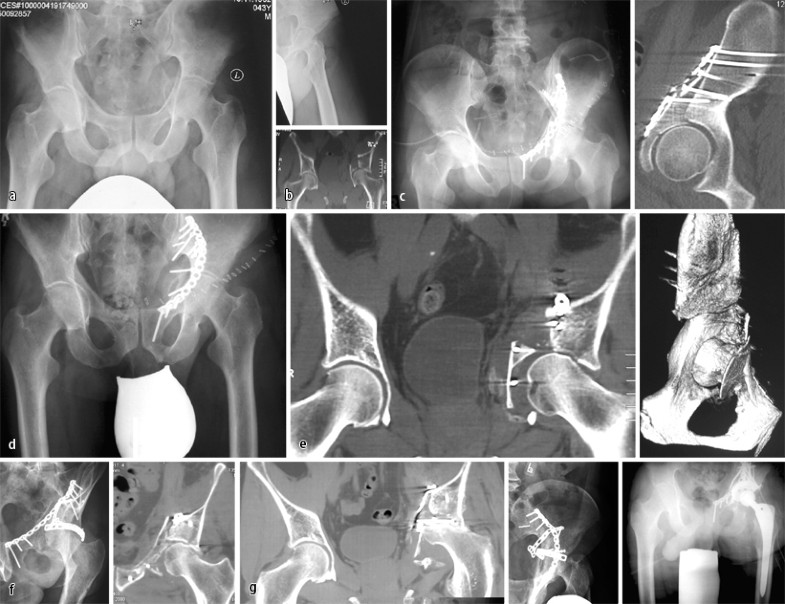

Der für die Reposition geeignete Zugang ist sicherlich eine wesentliche Voraussetzung für ein entsprechend gutes Resultat [13]. Lässt sich – trotz korrekter Zugangswahl – etwa bei einer seltenen Kombinationsfraktur der vorderen Azetabulumwand, des vorderen Pfeilers und der quadrilateralen Fläche (Abb. 7 a,b) ein grenzwertiges Repositionsergebnis durch unzureichende Stabilität nicht bis zur knöchernen Durchbauung halten, resultiert beim jüngeren Patienten nach Redislokation hieraus zwangsläufig eine Revisionsindikation unter primärem Gelenkerhalt. Problematisch ist dabei die sichere Fixation der quadrilateralen Fläche [11]. Kommt zudem eine posttraumatische Femurkopfnekrose hinzu, ist ein sekundärer Gelenkersatz unvermeidlich (Abb. 7 g), der bei entsprechendem Pfannendefekt meist einer Unterfütterung mit Eigenknochen und Spezialimplantaten bedarf. Nicht zuletzt wegen der schwierigen Ausgangssituation bei der posttraumatischen Arthrose und der vorbestehenden Narbensituation nach rekonstruktivem Voreingriff sind die funktionellen Resultate und die Standzeiten der sekundären Endoprothetik deutlich schlechter als bei der Prothetik bei primärer Koxarthrose [1, 11].

Ein primärer Gelenkersatz der Hüfte bei der Azetabulumfraktur des jüngeren Patienten ist lediglich bei simultanen Schenkelhalsfrakturen (Pipkin-IV-Fraktur) oder vorbestehenden Gelenkschäden zu erwägen. Ansonsten ist ein primärer endoprothetischer Gelenkersatz – mit [11] oder ohne Osteosynthese [1], häufig aber mit der Notwendigkeit, spezielle Implantate wie Pfannenabstützschalen einsetzen zu müssen – eine reliable Option für den älteren Patienten [13]. Der ansonsten potenziell anstehende Zweiteingriff wird so vermieden, die Ergebnisse des primären Gelenkersatzes scheinen über denen der sekundär erforderlichen endoprothetischen Versorgung zu liegen [1, 11].

Fall 6, 43-jähriger Patient, a,b AO-Verletzung 62B3.2 mit erheblicher Trümmerzone der vorderen Azetabulumwand, des vorderen Pfeilers, der quadrilateralen Fläche, c inkomplette Reposition (intraartikuläre Stufe, Pfanneninkongruenz), d,e weitere Dislokation unter Mobilisation, f residuale Inkongruenz der Hüftpfanne nach Revision, g Teilimplantatentfernung und Hüft-TEP, weitere Erläuterungen s. Kasuistik

Fall 6

Bei dem 43-jährigen Mann (AO 62B3.2) bestand eine erhebliche Trümmerzone der vorderen Azetabulumwand, des vorderen Pfeilers sowie der quadrilateralen Fläche.

Aufgrund des inkompletten Repositionsergebnisses mit intraartikulärer Stufe und Inkongruenz der Pfanne kam es unter Mobilisation zu einer weiteren Dislokation. Nach der Revisionsoperation über einen doppelten Zugang (ilioinguinal und Kocher-Langenbeck-Zugang) lag dennoch eine residuale Inkongruenz der Hüftpfanne vor.

Im weiteren Verlauf entwickelte sich binnen 6 Monaten eine Femurkopfnekrose mit konsekutiver Indikation zur Teilimplantatentfernung und Hüft-TEP (Abb. 7).